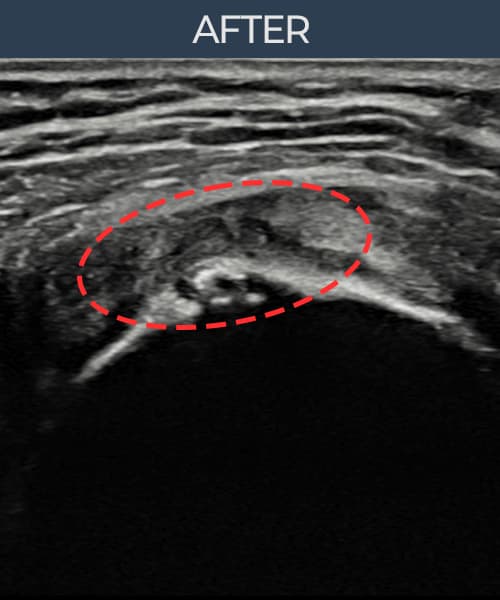

右侧 冈上肌腱 石灰化肌腱炎

10mm × 7mm